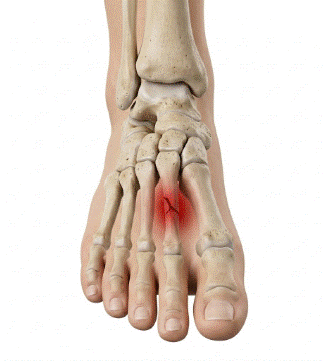

Fractura de estrés del metatarsiano: biomecánica y prevención

La fractura de estrés del metatarsiano es una lesión por sobrecarga frecuente en deportistas, militares y cualquier persona sometida a un aumento brusco de la carga de impacto sobre el pie, y su incidencia ha crecido de forma paralela al auge del running y los deportes de alta demanda física. A diferencia de las fracturas […]